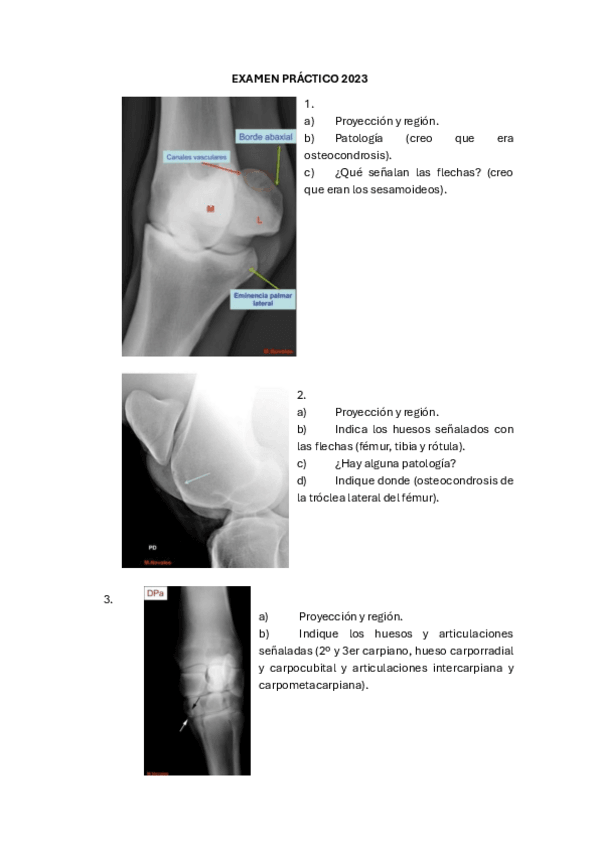

He publicado nuevos examenes de 3º Diagnóstico Por la Imagen: examenes-practico-dx.pdf